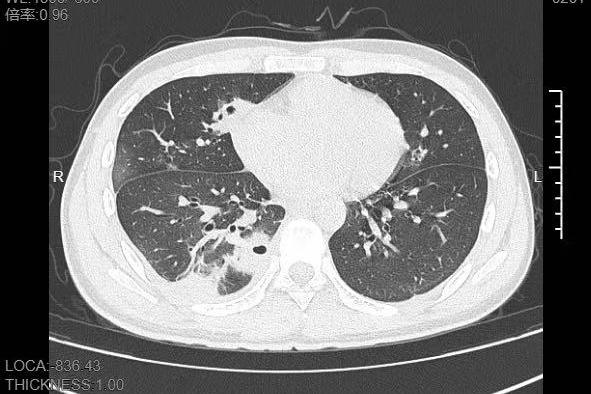

"罪魁祸首就是那颗被挤掉的痘痘。"丁群力解释,"这颗痘痘长在脸部'危险三角区',挤痘痘时的压力把细菌推进了血管,引发了败血症,接着细菌顺着血流跑到肺部,侵蚀肺组织。"